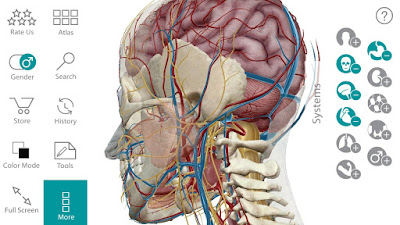

-Visible Body ® là một công ty phát triển phần mềm tạo giải phẫu học từng đoạt giải thưởng và các sản phẩm học tập sinh lý học.Trong đó, phần mềm Visible Body Human Anatomy Atlas là một trong những thành công nhất. Ứng dụng này phát triển trên cả nền tảng máy tính và di động.Với những hình ảnh sinh động và trực quan, thật dễ dàng để bạn có thể làm chủ kiến thức giải phẫu cơ thể người.

-Ứng dụng này bao gồm các mô hình giải phẫu 3D với hơn 6000 hình ảnh 3D từ tất cả các hệ thống cơ thể:Cá nhân mình thấy đây là một ứng dụng rất hay, ứng dụng được viết bằng tiếng anh rất tiện cho việc học từ ngữ chuyên ngành luôn ( nếu tiếng anh của bạn mù tịt như mình thì có thể vào đây dịch ) thứ hai ứng dụng này có dung lượng tuy nhỏ (chỉ hơn 200 mb) nhưng đầy đủ các chức năng của một ứng dụng giải phẫu 3D chuyên nghiệp như xoay mô hình 360o , ẩn các bộ phận được chọn, vẽ thêm chi tiết vào mô hình vv… đặc biệt khi bạn chọn vào một bộ phận, sẽ có đường chỉ dẫn đến bộ phận đó và có phần miêu tả khá đầy đủ (cũng bằng tiếng anh ) ở phía dưới.